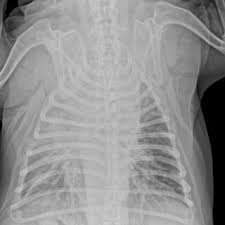

Q1: 갈비뼈 금은 X-ray에서 안 보일 수도 있나요?

A1: 네, 초기에는 X-ray에서 잘 보이지 않는 경우도 있어 증상과 촉진이 중요합니다.